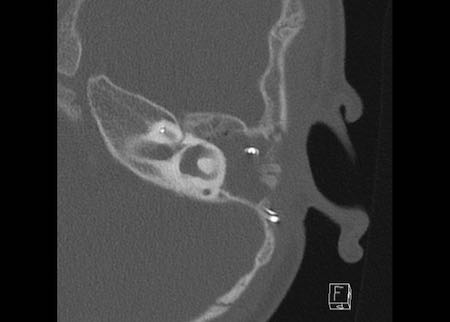

Bên trái là hình ảnh của một bé gái 2 tuổi.

Các hình ảnh từ kết quả chụp CT được thực hiện trước khi cấy ốc tai điện tử.

Quan sát thấy dị dạng nhẹ ở đỉnh ốc tai – không có sự phân tách giữa vòng thứ hai và vòng thứ ba, và trụ ốc tai xương vắng mặt.

Cống tiền đình bình thường.